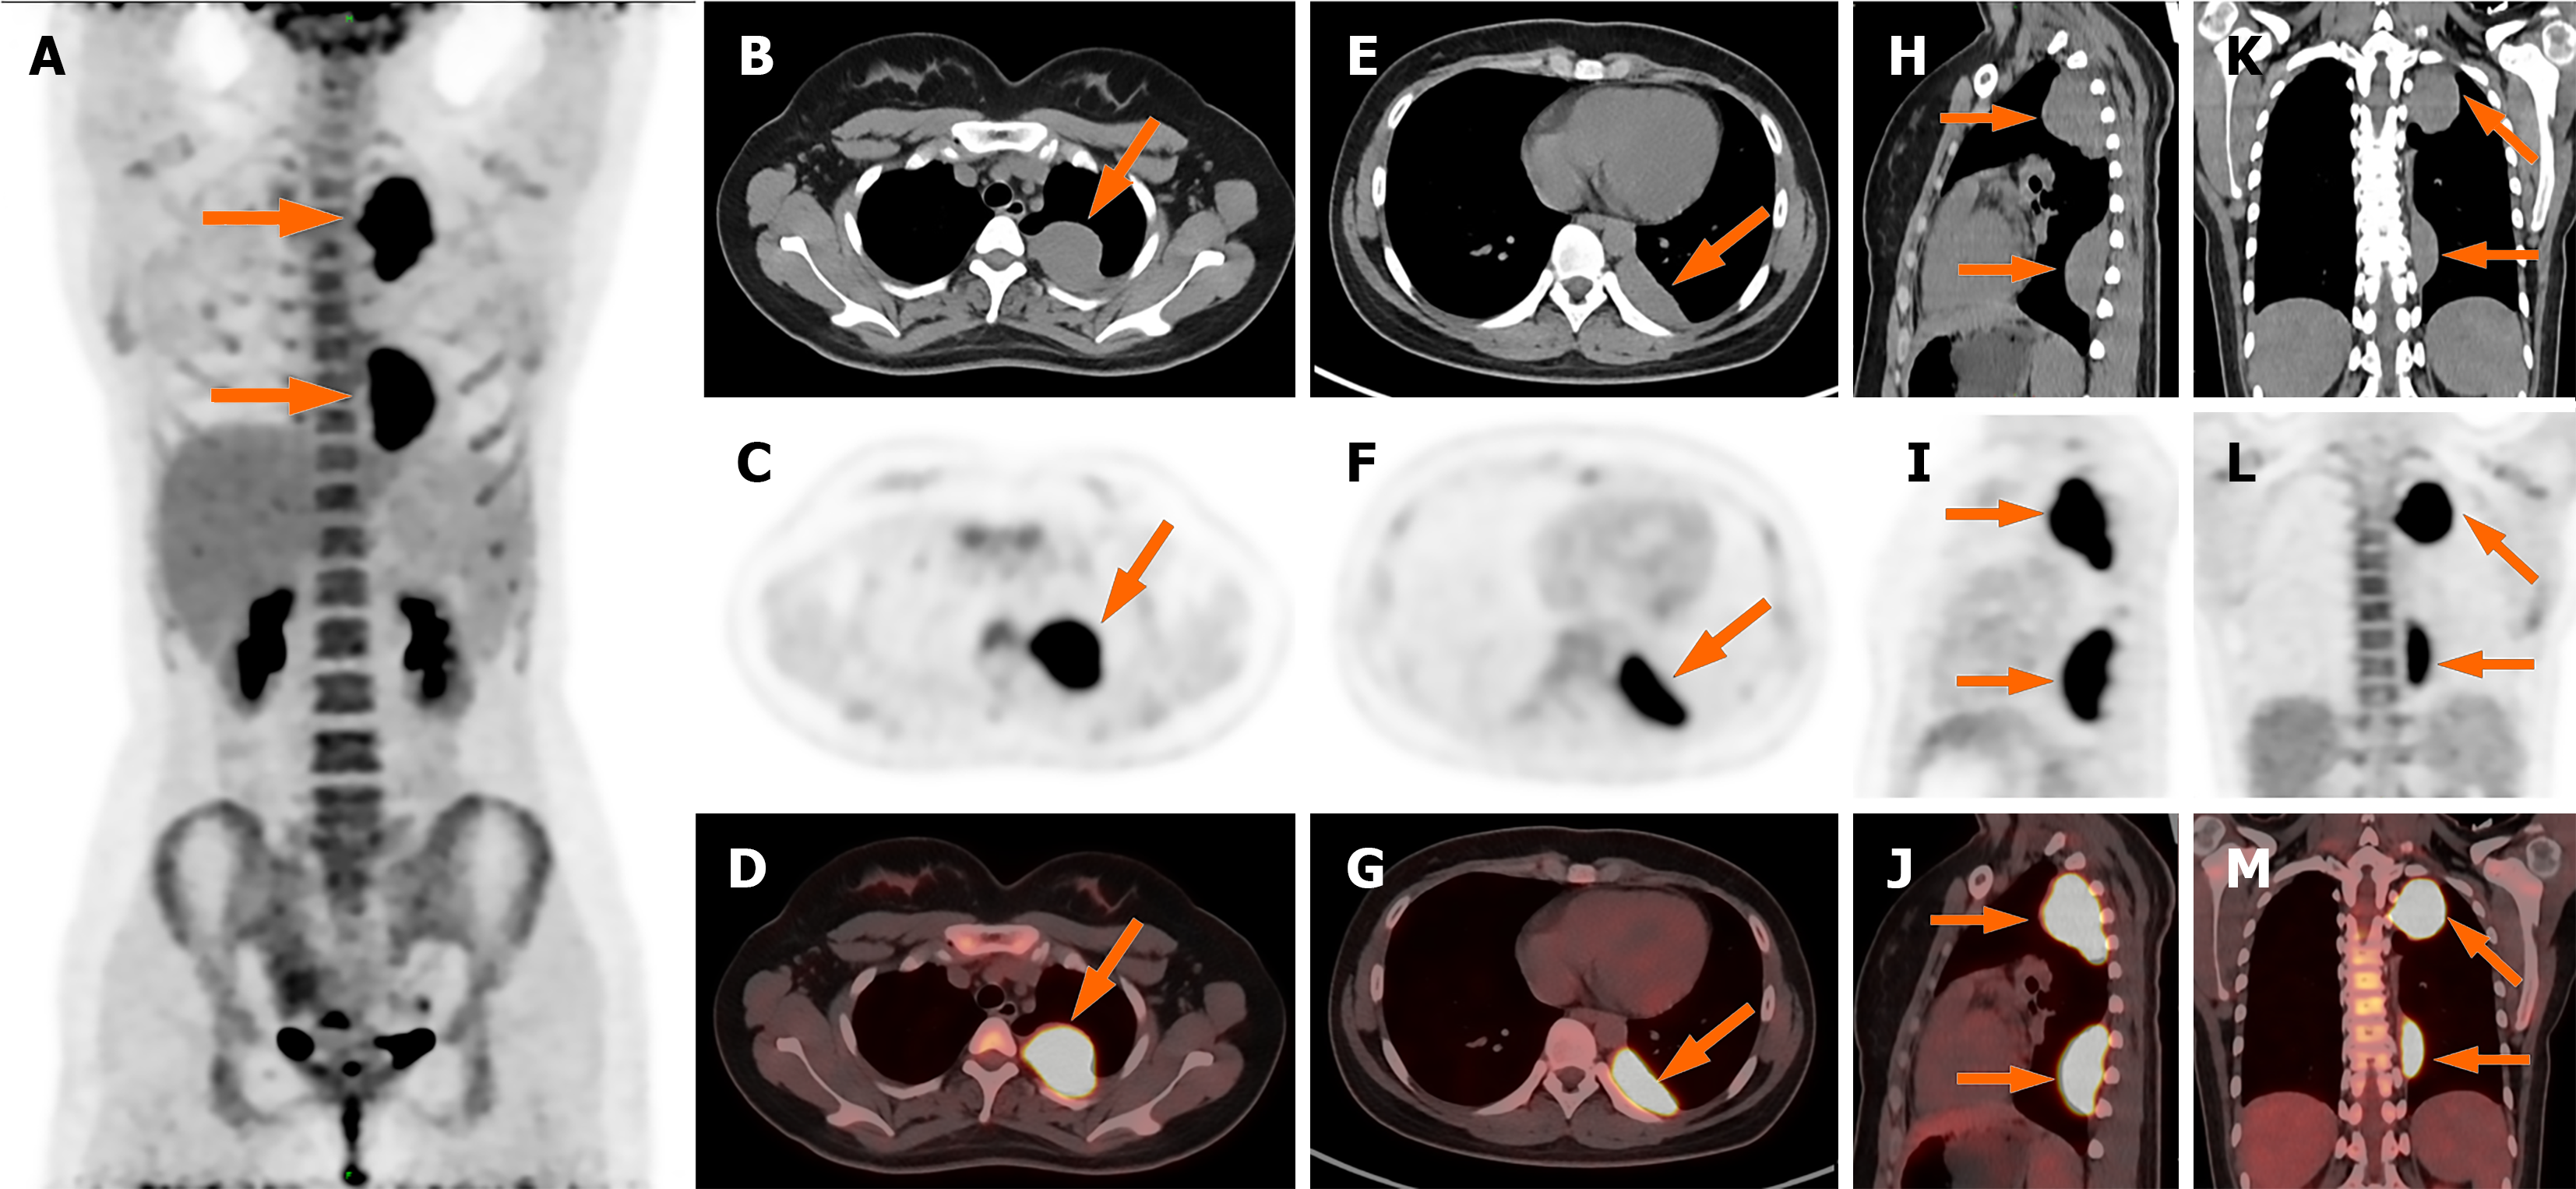

Figure 3 Whole body positron emission tomography/computed tomography images.

A: Maximum intensity projection image showed increased F-18 fluorodeoxyglucose (FDG) uptake in the lesion (arrow). No other FDG-avid lesions were detected elsewhere in the body. Lesion 1: B-M: Axial (B–D); Lesion 2: Axial (E–G), sagittal (H–J), and coronal (K–M) PET/CT demonstrated abnormally elevated FDG uptake in the lesions (SUVmax 14.0 and 13.7, respectively).